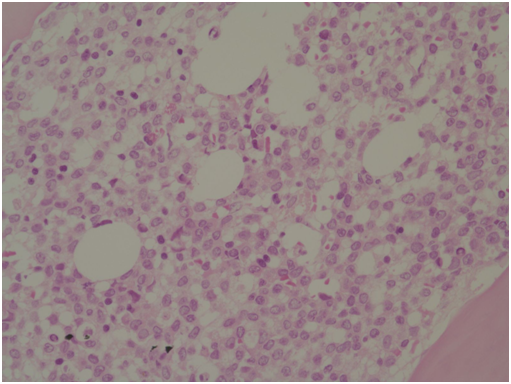

A 14-year-old girl was admitted for neck pain and fever for 5days. Physical examination revealed swelling of left neck. Her blood cell counts were as follows: WBC, 1.59×109/L; Hb,6.7g/dL; and platelet, 68×109/L. Peripheral blood smear showed 4% of blasts. Bone marrow (BM) aspirate showed increased blasts, counted up to 74% of all nucleated cells. The leukemic blasts showed medium to large-size, prominent nucleoli, relatively abundant basophilic cytoplasm with occasional azurophilic granules (Figure 1). BM biopsy showed hypercellularity with diffuse infiltration of blasts (Figure 2). The leukemic blasts were immuno histochemically reactive for myeloperoxidase (MPO) (Figure 3). Flow cytometric analysis showed leukemic cells positive for CD13, CD33, CD64, CD11c, HLA-DR, cMPO and CD7, and negative for CD34 and terminal deoxynucleotidyl transferase (TdT). A cytogenetic study revealed the following chromosome abnormalities: 46, XX, t(5;11)(p12p15.3;q13q23), t(8;12)(q22;q13), add(14)(p12),-17, +mar[10]/46, XX[10] (Figure 4). In addition, interphase fluorescence in-situ hybridization (FISH) analysis using a MLL LSI dual color, break-apart probe demonstrated 76% of cells with break-apart signals (Figure 5). FISH study for EGR1/D5S23showed normal pattern on interphase cells; however, one D5S23 (5p15.2) signal was observed at chromosome 11 on metaphase cells (not shown). These results could be suggestive of t(5;11) with four-break rearrangement, which correlate with chromosomal results. Recurrent gene rearrangements in acute leukemias by multiplex reverse transcriptase-polymerase chain reaction (RT-PCR) including major and minor BCR/ABL1, PML/RARA, and RUNX1/RUNX1T1 genes was negative. FLT3-ITD, NPM1, and KIT mutation tests showed negative results. Based on above findings, the patient was diagnosed as having acute myeloid leukemia with variant MLL translocation. Concurrent neck computed tomography (CT) scan revealed diffuse superficial and deep infection of left neck with bilateral cervical lymphadenopathy. Chemotherapy was scheduled, but withheld due to persisting high fever. On follow-up CT scan, abscess formation of left neck was suspected. Despite intensive antibiotic and supportive therapies, the patient succumbed due to septic shock 28 days after admission.

Figure 2 BM biopsy showing diffuse infiltration of blasts (H&E stain,×400).

Figure 3 Blast cells with positivity for myeloperoxidase (MPO stain,×400).